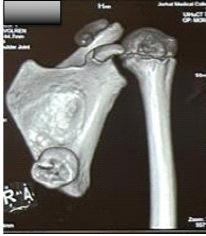

Symptomatic Ventromedial Scapular Osteochondroma Presenting with Restriction of Shoulder Movements: A Case Report

Jaydev Barapatre , Mondeep Gayan , Zaheer Islam , Abhijeet Dhurwe , Chao Rochek Buragohain

………………………………p.212-216